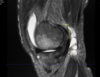

3 months after his initial injury an MRI was ordered to further characterize his knee pain. The MRI was most notable for subchondral edema in the medial femoral condyle, medial meniscal tear, medial femoral condyle chondrosis and 2 loose bodies in the intercondylar notch anterior knee with a significant effusion.